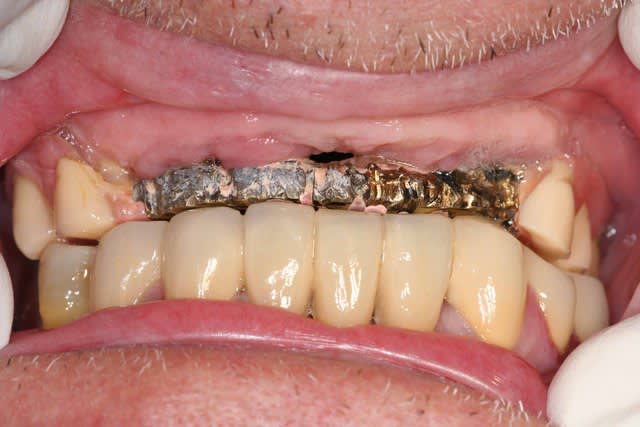

1er cas: une belle réussite chirurgicale et un massacre prothétique

2ème cas: une belle réussite prothétique(aucune mobilité, esthétiquement acceptable malgré la position des implants) et un massacre chirurgicale (6 ans)

ça vous convient comme échec?